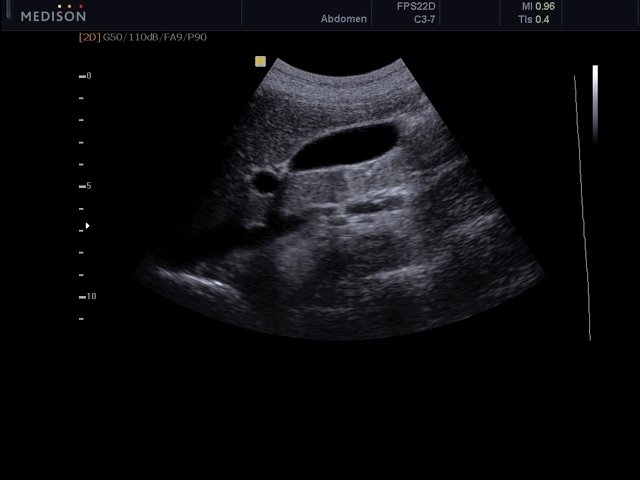

[EN] Эхограмма №471: Желчный пузырь в B-режиме (конвексный датчик 3-7 МГц).

Изображение получено с помощью УЗ аппарата MySono-U5 (снят с производства).